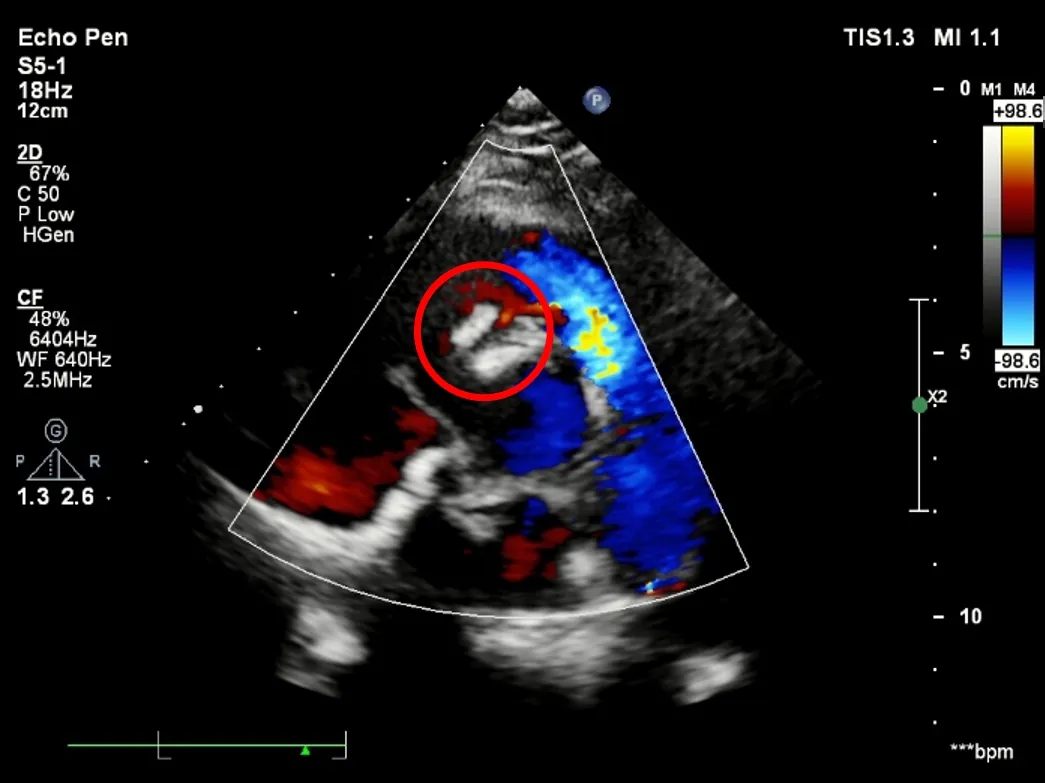

释放后超声

超声下可见室水平和房水平都无残余分流

心脏彩超:心脏超声下可见两个封堵器双盘稳固夹持,无残余分流;

术后1个月心脏超声,房室水平皆无残余分流